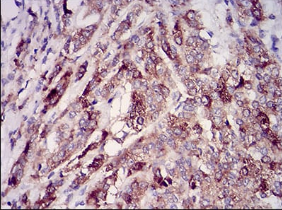

IHC    1/200 - 1/1000